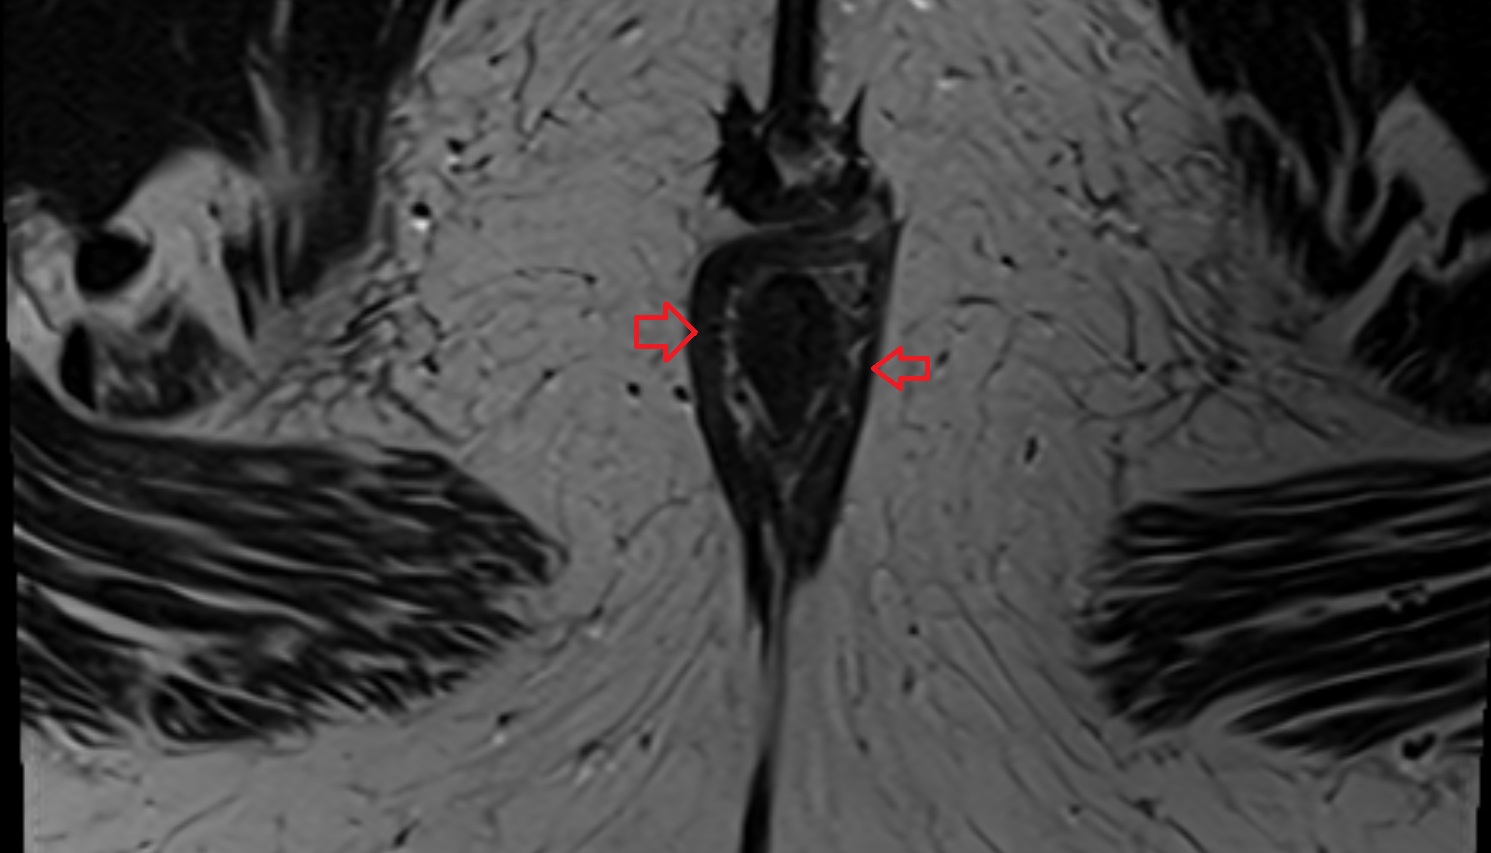

- Peripheral zone of prostate

- Anterior Fibromuscular Stroma of prostate

- Central zone of prostate

- Transitional zone of prostate